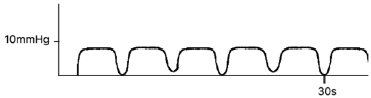

Durante o atendimento de um paciente que evoluiu para parada cardiorrespiratória no pronto-socorro e que recebe reanimação cardiopulmonar, o seguinte traçado da capnografia em forma de onda é observado:

Baseado nesta informação e segundo o ACLS, a conduta mais adequada é